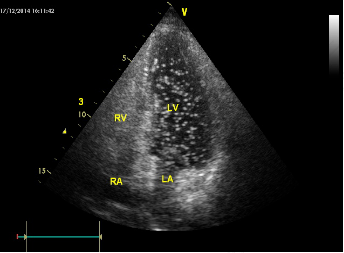

超声造影或声学造影主要是通过造影图像能清晰的显示微循环血流特性,因此可清晰的观察到某些肿瘤是具有良性肿瘤或恶性肿瘤的倾向,从而作出较为明确的定性诊断。

利用声学造影检查可以较为有效的诊断出早期肿瘤的恶性肿瘤病灶,对于恶性肿瘤的检出率也较高。声学造影或超声造影是目前较为先进的医学影像技术,其优势为可以实时的进行动态观察,具有分辨率高,而且无创,无辐射以及重复性好的独特优势。